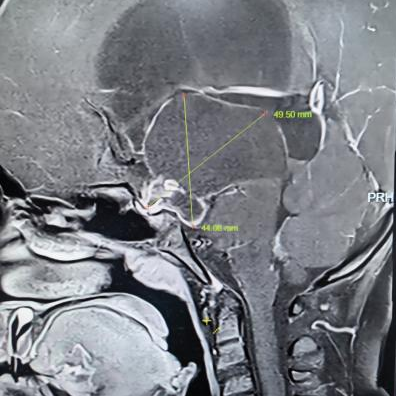

术前核磁共振检查

为精准掌握肿瘤情况,团队为欢欢完善了垂体MRI平扫+增强检查及相关激素水平检测。结果显示:肿瘤体积超过4厘米,形如鸡蛋,已严重压迫视神经与垂体,突入第三脑室,并与周围重要神经血管结构紧密粘连。颅咽管瘤是一种起源于颅底的先天性良性肿瘤,因体积大、位置深,且毗邻下丘脑、视神经、垂体等重要结构,手术切除难度极高,稍有不慎就可能导致失明、终身内分泌紊乱甚至有生命危险。